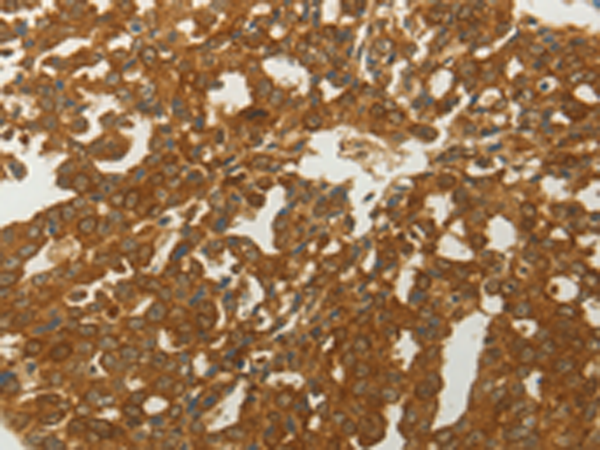

分类: 科研抗体货号: P11019别名: MCT14应用: WB,IHC反应种属: Human, Mouse